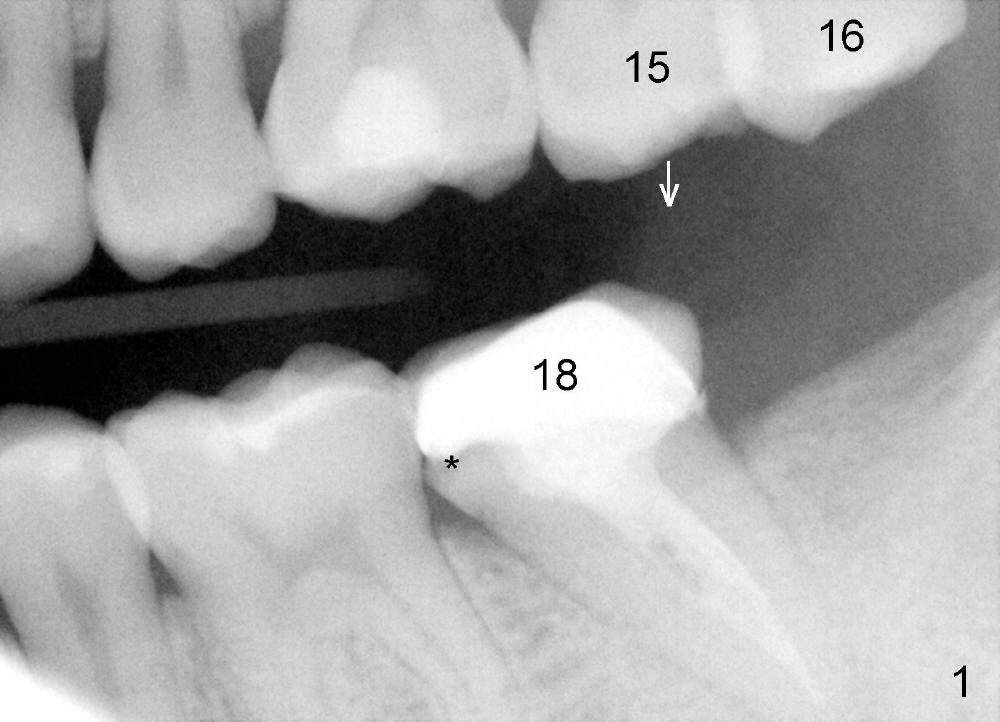

为什么那个牙冠会脱落呢?本来第二磨牙垂直高度就不足,另外似乎对合牙(图一,:15)向下面伸长(箭头),占据下牙空间,牙冠高度不够,最好方法便是使用微型植牙(图五箭头)和橡皮筋(*),持续对对合牙施加压力,它慢慢地往上移动(intrusion)。刚四十岁的冷先生对新鲜事物容易接受,正好他的保险还保这项治疗(局部矫正)。两个月后,牙齿移位不少(图六),总共四个月我们目的达到了(开始做牙冠):其实矫枉过正(图七),正是我们期待,不过告诉实验室做牙冠时不必使用所有间隙,让对合牙自己下降。